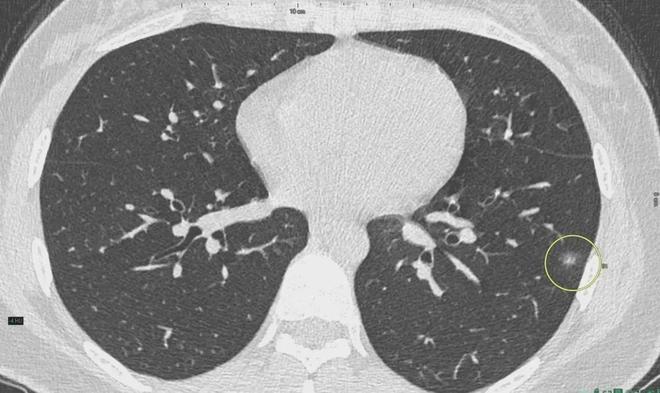

肺結(jié)節(jié)是一種常見的肺部疾病,其發(fā)病率逐年上升,雖然肺結(jié)節(jié)多數(shù)情況下是良性的,但也有可能惡化為肺癌,了解肺結(jié)節(jié)的形成原因?qū)τ陬A(yù)防和治療具有重要意義,本文將為您詳細(xì)解析肺結(jié)節(jié)的形成機(jī)制。

肺結(jié)節(jié)的形成原因

1、環(huán)境因素

環(huán)境因素是肺結(jié)節(jié)形成的重要原因之一,長期暴露于污染環(huán)境中,如空氣污染、化學(xué)污染等,可能導(dǎo)致肺部吸入有害物質(zhì),從而引發(fā)肺結(jié)節(jié),長期接觸石棉、硅塵等職業(yè)環(huán)境因素也可能增加肺結(jié)節(jié)的發(fā)病風(fēng)險(xiǎn)。